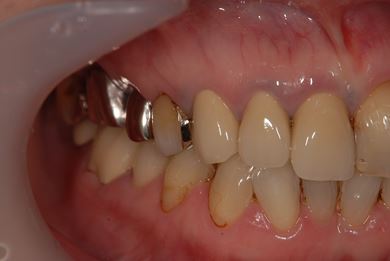

インプラントの症例写真 IMPLANT

骨再生スピードインプラント治療+セラミック治療

| 主訴 | 左上の歯に以前から歯周病があり、多少のぐらつきがあったが、ここにきていよいよ限界になりました。食事に影響があるので、インプラントを視野に、とりあえずは抜歯をと思っています。 | ||||||||||||||||||||||||||||||||

| 治療方針 | サイナスリフトにて上顎洞を拳上し、インプラント治療を可能にする。抜歯と同時にインプラント埋入を行い、治療期間を短縮する。 | ||||||||||||||||||||||||||||||||

| 治療内容 | インプラント9本(抜歯即日スピードインプラント、サイナスリフト)、ハイブリッドセラミッククラウン12本(ハイブリッドセラミック用土台3本) | ||||||||||||||||||||||||||||||||